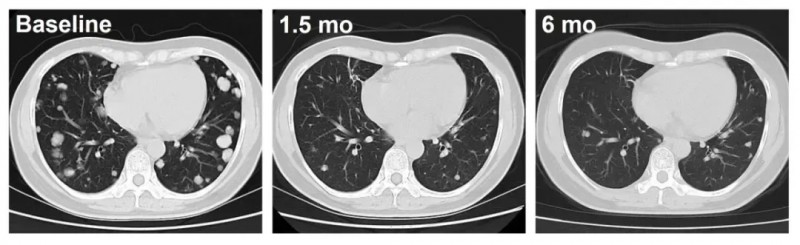

具体来看,C010号患者(DL3)的疗效更为持久,经12个月以上跟踪,肿瘤持续稳定缩小;另一例C023号患者(DL4)治疗仅1.5个月,肺转移病灶便出现深度应答,影像学可见肿瘤显著缩小。

▼C010号患者治疗前后影像学对比

▼C023号患者治疗前后影像学对比

▲图源“ASCO”,版权归原作者所有,如无意中侵犯了知识产权,请联系我们删除